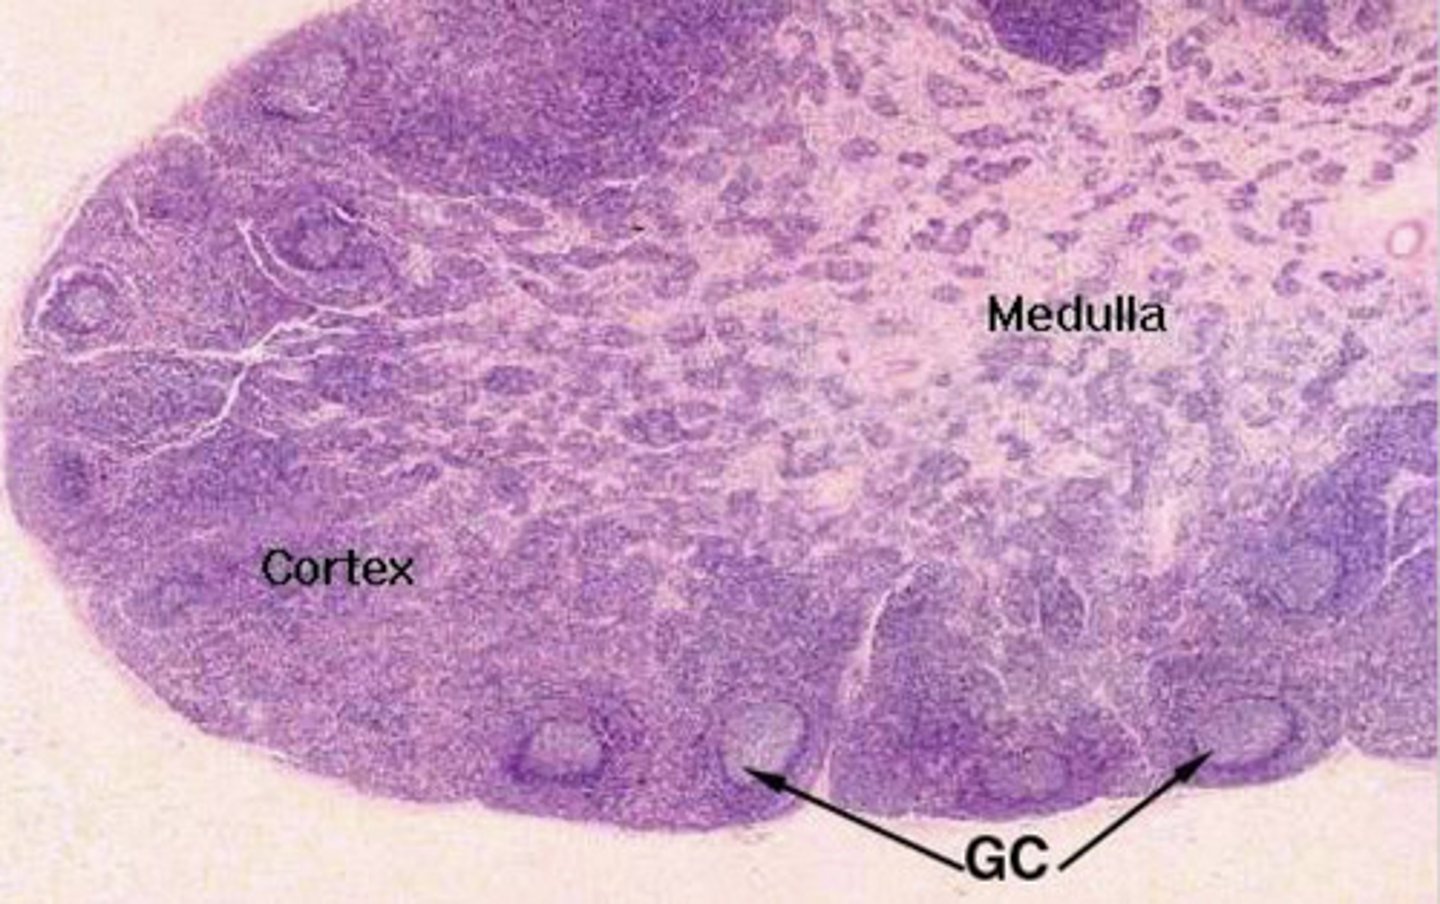

are lymph nodes tubular or parenchymal?

parenchymal-

cortex- follicles with mantle, germinal center, B lymphocytes

medulla- capillaries

what is the structure of lymph nodes?

cortex

what part of the lymph node has follicles with B cells?

interfollicular tissue in the cortex

what part of the lymph node has T cells?